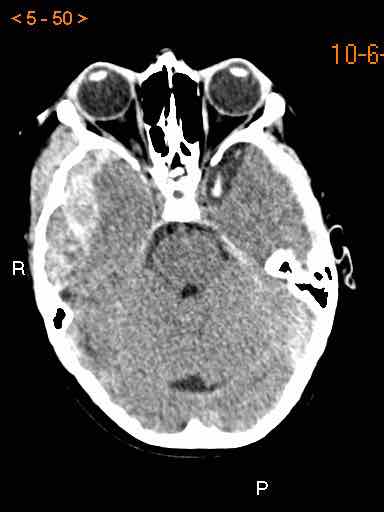

Hình ảnh CT

- Ghi nhận khối xuất huyết hình thấu kính vùng thái dương-đỉnh

- Khối xuất huyết bị giới hạn bởi các đường khớp sọ

- Gãy xương sọ kèm theo

- Dấu hiệu xoáy (swirl sign) cho thấy sự thoát mạch của máu vào trong khối tụ máu. Dấu hiệu này đại diện cho máu tươi chưa đông (giảm tỷ trọng) bao quanh bởi máu đã đông (tăng tỷ trọng hơn).

- Thoát vị dưới liềm não theo chiều ngang và thoát vị móc hải mã.

Bệnh nhân sau đó được phẫu thuật mở hộp sọ và động mạch màng não giữa bị rách đã được đốt cầm máu.

Kết quả lâm sàng tốt.